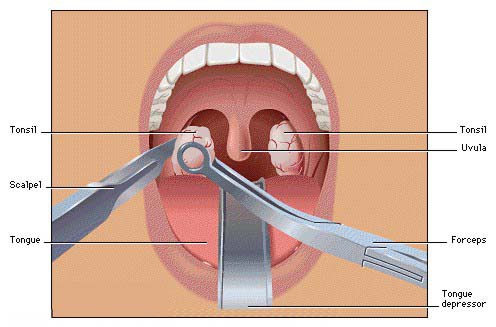

Overview

Package includes:

Days in hospital : 2 to 3 Days (For patient and one attendant)

Days in hotel : 5 Days (For patient and one attendant)

Room type in hospital : Shared

Room type in hotel : Private

Hotel category: Standard

Value added benefits of the Tonsillectomy: